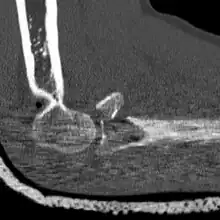

CT scan demonstrating the Mason type III radial head fracture

CT scan showing a radial head fracture